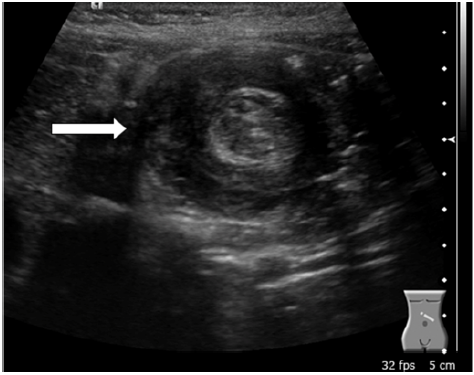

Uma menina de 10 meses de vida foi levada ao departamento de emergência com vômitos persistentes, letargia, distensão abdominal e choro inconsolável. Optou-se então, pela realização de exames laboratoriais e de uma ultrassonografia de abdome total. Com base na imagem apresentada, qual é a principal patologia?